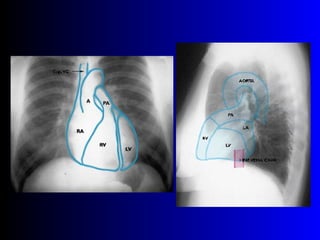

Este documento describe la técnica para realizar una telerradiografía de tórax normal e identifica las estructuras visibles en la imagen, incluyendo los huesos, vasos sanguíneos, grasa, tejido subcutáneo, pulmones y mediastino. Explica que es importante centrar la imagen en los ápices pulmonares, senos costodiafragmáticos e inspiración profunda para una visión clara de las estructuras.